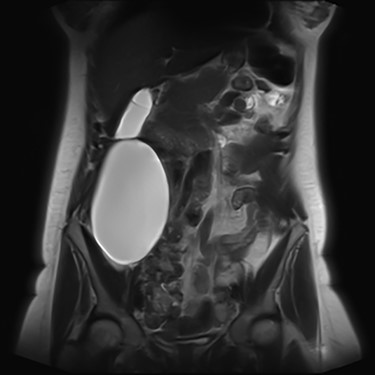

We present an extremely rare and isolated case of primary mixed serous and mucinous cystadenoma in a 49-year-old otherwise fit and healthy female patient. She was referred to our consultant with a history of discomfort on the right side of her abdomen for few years, which increased gradually with no other complains. The patient had further investigations conducted including computed tomography (CT) (Figs 1 and 2) that demonstrated the position and size of the lesion. The magnetic resonance imaging (MRI) revealed a large cystic lesion in the right retroperitoneal region shown in Figs 3 and 4. Her full blood count, inflammatory markers, urea and electrolytes and liver function tests were within the normal limit. Consequently, the patient had a laparoscopic resection of an isolated retroperitoneal cyst. At surgery, the cystic lesion seemed to be arising from mesentery and the lesion was dissected intact and completely excised. Histopathology revealed a benign mixed serous and mucinous cystadenoma as shown in Fig. 5. The patient was discharged from the hospital with no complications and fully recovered on follow-up review. Patient was discussed in a multidisciplinary team meeting and the recommendation was for no further management.

Primary retroperitoneal serosal cystic lesions are uncommon heterogeneous clinical entities with no definite incidence [10]. The actual pathogenesis is not well understood, although one of the proposed hypotheses considers it to be an embryological remnant of the urogenital apparatus with epithelial and mesothelial tissues. These cysts oftentimes attain a very large size before becoming symptomatic [3].

Serological investigations are not helping with providing a definitive diagnosis. Tumour markers such as, carbohydrate antigen (CA) 19–9, CA 15–3, CA 125, carcinoembryonic antigen (CEA), alpha feta protein have not been shown to be sensitive or specific. Some cases demonstrated an increase in CEA and CA 19–9 in associated with PRMC. However, these are isolated case studies. With regard to radiological investigation, the ultrasonography lacks specificity [11]. Radiological imaging, such as MRI and CT, plays an important role in describing and assessing the disease’s characteristics and the involvement of adjacent or distant structures of the mass. None of the modalities can exclude the malignant potential of the retroperitoneal masses [9], as the diagnostic value of CT and MRI is similar [12]. Predominantly male patients and the patients who present with solid nodules in the cyst on their radiology images have strong association with malignancy [13].